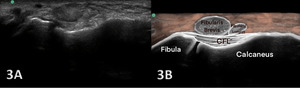

NORMAL VIEW IN OBLIQUE LONGITUDINAL AXIS (LAX): CALCANEOFIBULAR LIGAMENT (CFL)

Figures 3A and 3B Oblique Longitudinal/LAX Axis View: Dorsiflexion of the foot tensions the CFL and makes the fibers more visible as they reach from the fibula to the calcaneus. The peroneal/fibular tendons are superficial to the CFL. A careful downward rotation of the probe from a SAX image of peroneal tendons is needed for a LAX of the CFL. A normal, intact CFL shows a curved course with an echogenic fibrillar structure located between the calcaneus and peroneal tendons. If the ankle is kept in a relaxed and static position, the CFL will look slightly concave. With ankle dorsiflexion and inversion, the CFL is being stretched and will straighten resulting in a lifting up of the peroneal tendons a small amount called a “trampoline sign”. Lifting of the tendons and stretching of the ligament is a sign of ligament continuity.